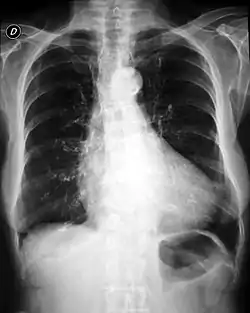

![]() تضخم في القلب (أشعة-اكس) أحد صفات متلازمة كانتو تضخم في القلب (أشعة-اكس) أحد صفات متلازمة كانتو | |

متلازمة كانتو (خلل التنسج العظمي الغضروفي) [4] هي حالة نادرة تتميز بفرط الشعر، خلل التنسج العظمي الغضروفي، و تضخم في القلب. [5][3] تم وصف أقل من 50 حالة في الأدب. أنها ترتبط بطفرة في جين ABCC9 الذي يرمز لبروتين ABCC9. [3]

الملامح الرئيسية لهذه الحالة هي فرط الشعر، تضخم غضروفي عظمي، تضخم القلب . وهناك أيضا مميزة سحنة. وتشمل الميزات الأخرى القناة الشريانية المفتوحة، تضخم الخلقي من البطين الأيسر، والانصباب التاموري. [6]

يمكن تشخيص هذه الحالة عن طريق الاختبارات الجينية . [10] علاوة على ذلك، قد يساعد تخطيط صدى القلب والأشعة السينية في التشخيص. [2]